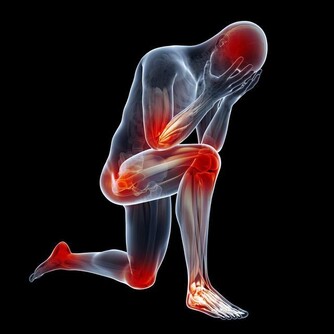

我們每個人對炎症都不陌生,手上不小心劃傷的傷口可能會發炎,感冒的時候扁桃體可能發炎,吃壞了肚子會有腸炎,還有令人感到難纏的關節炎……總之,全身各個器官組織都可能出現炎症,只是或輕或重罷了。